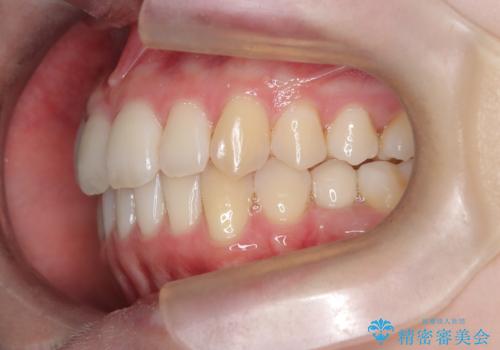

【インビザライン】 前歯の反対咬合を治したい

- 20代女性

- 2年

左下5番は先天性欠損のため乳歯は抜歯しインプラントにて欠損補綴しています。